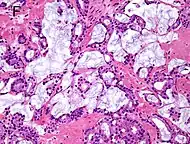

Mucinous adenocarcinoma 0.2%[12]

• ≥25% of tumor shows extracellular mucin[1]

• Intraluminal mucinous material does not qualify[1]

• No extraprostatic origin found[1]

Tumorous glands:

• 34βE12- and p63-[1]

• PSA+ and CK8/18+[1]

4+4=8 for irregular cribriform glands floating in mucin.[1]